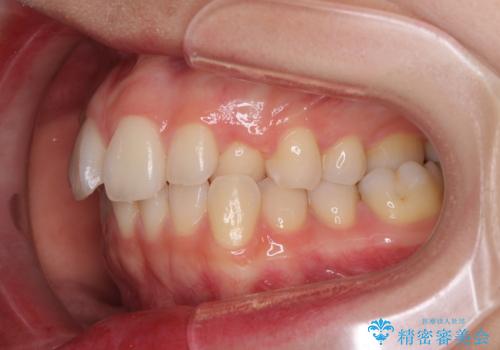

- 前歯のクロスバイトや残存している乳歯を気にして来院された患者様です。

上顎骨の幅が下顎骨よりも小さいので、拡大装置により骨幅を広げて上下関係を改善し、その後インビザラインにて歯並びを整えることとしました。

上下の骨幅を改善したことで、スムーズに歯列矯正を行うことができました。